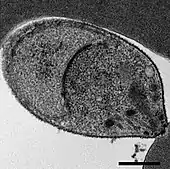

Microscopic aspect of Plasmodium knowlesi in a blood smear

Giemsa-stained thin blood smears of human red blood cells infected with Plasmodium knowlesi

Malaria is traditionally diagnosed by examining Giemsa-stained blood films under a microscope; however, differentiating P. knowlesi from other Plasmodium species in this way is challenging due to their similar appearance.[11] P. knowlesi ring-stage parasites stained with Giemsa resemble P. falciparum ring stages, appearing as a circle with one or two dark dots of chromatin.[17] Older trophozoites appear more dispersed, forming a rectangular-shape spread across the host cell called a "band-form" that resembles the similar stage in P. malariae.[17] During this stage, dots sometimes appear across the host red blood cell, called "Sinton and Mulligans' stippling".[17] Schizonts appear, similarly to other Plasmodium species, as clusters of purple merozoites surrounding a central dark-colored pigment.[17]